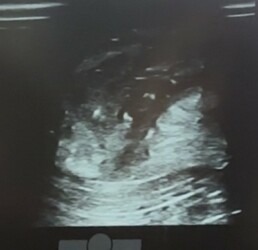

- Ultraschall, um Größe, Kapselbildung und Inhalt zu beurteilen

Bei Cleo zeigte der Ultraschall eine abgekapselte Höhle mit Entzündungsprodukten – ein klassischer Abszess.